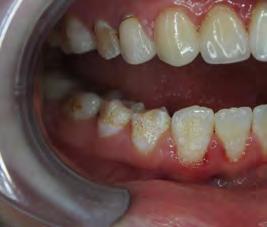

Two authors had access to the data and all information was de-identified. Study personnel made no contact with patients at any time throughout the study, and no PHI was recorded. Re corded data included diagnosis (clinical and/or pathologic), basic demographics (age, gender), and current prescription medica tions. For cases that were not biopsy-proven, the standard clinic protocol is that the clinical presentation must exhibit the charac teristic white Wickham striae for a patient to be given the clinical diagnosis of OLL or OLP (Figure 1). Any clinical diagnosis of OLL or OLP was rendered by one of four oral medicine experts in the Oral Medicine Clinic, and biopsy was performed in cases with any doubt.

Figure 1. Example of characteristic Wickham striae and reticular pattern on buccal mucosa used to clinically diagnose OLL and OLP cases. Erythematous areas also seen. Figure 2. Frequency and percent of study patients using specific medications with color-coded drug classes.